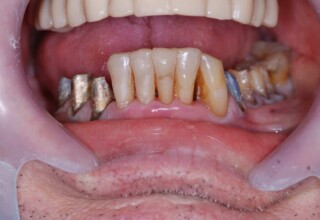

Extensive case with crowns in almost all teeth

Extensive case with crowns in almost all teeth due to extensive wear, old restorations, posterior root canals and aesthetic concerns. Patient (60years old) presented with intense bruxism which he never had treated. Consequently, he obtained very deep cervical abrasions which jeopardized tooth integrity. Restorations (fillings) were executed mainly with adhesive resinous materials and three custom cast post and cores. Temporary crowns were placed to evaluate the desired size, shape and position of the teeth before permanent crown fabrication.

Initial smile

Final Smile